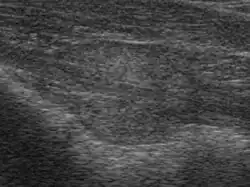

Die Untersuchungsmöglichkeiten der Prostata sind zwar mittlerweile recht vielfältig geworden, aber eine Hauptfragestellung, nämlich ob die Prostata durch einen bösartigen Tumor befallen ist oder nicht, ist nach wie vor zumindest mit den nichtinvasiven Methoden wie dem Ultraschall oder der Computertomographie nur unsicher zu beantworten. Die Prostata des älteren Mannes neigt zur Knotenbildung, und es fällt schwer, mit nichtinvasiven Maßnahmen gutartige von bösartigen Knoten zu unterscheiden. Die Elastographie ist ein neues bildgebendes Verfahren, das Tumorareale aufzeigen und gezielt Gewebeproben entnehmen kann. Auch das sogenannte HistoScanning ist ein neues, ebenfalls ultraschallgestütztes Verfahren zur Detektion von Tumorarealen, um eine gezieltere Prostatabiopsie zu ermöglichen. Bisher ist dieses Verfahren jedoch nur an wenigen Kliniken in Deutschland verfügbar.

Die Prostata kann mit einem Finger rektal ertastet werden. Als bildgebende Verfahren finden bisher Ultraschall, Magnetresonanztomographie (MRT) und Computertomographie (CT) Anwendung. Als spezielles bildgebendes Verfahren zur Diagnose von Prostatakrebs steht die Positronen-Emissions-Tomographie (PET) zur Verfügung, beispielsweise mit 18F-Cholin als radioaktiv markierter Substanz (Tracer), einer Ammoniumverbindung mit dem radioaktiven Fluor-Isotop 18F. Bei Verdacht auf Veränderungen kann eine Biopsie der Vorsteherdrüse mit einer sogenannten Prostatastanze vorgenommen werden. Mit der Elastographie kann wegen der unterschiedlichen Härte Krebsgewebe von Normalgewebe unterschieden werden, so dass gezielt Gewebeproben entnommen werden können. Das HistoScanning misst nicht die Elastizität des Gewebes, sondern durchmustert das Gewebe und greift auf eine große Prostata-Gewebedatenbank zurück, indem mit Hilfe eines Computers ein Datenvergleich mit den Ultraschalldaten und der Datenbank erfolgt. Krebsverdächtige Strukturen werden dabei farblich gekennzeichnet und ermöglichen so eine gezielte Punktion bei der Biopsie.